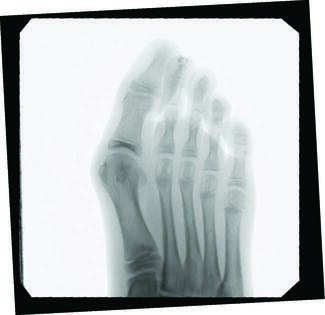

Jeffrey E. McAlister, DPM, FACFAS; Keegan A. Duelfer, DPM

Interest continues to grow in minimally invasive surgical (MIS) techniques throughout foot and ankle surgery in hopes of decreasing surgical trauma, mitigating certain risks, and perhaps allowing for earlier return to activity. Here the...